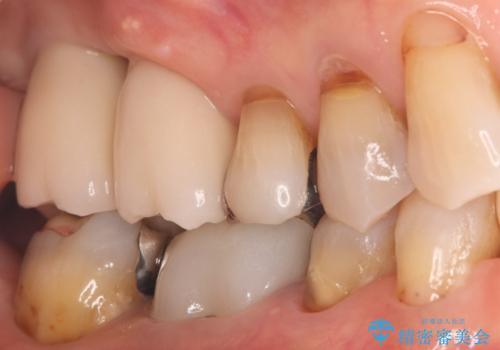

その後、インプラントと骨がしっかりと結合するのを待ってから、最終的な被せ物(クラウン)を装着。これにより、重度歯周病で失われた2本の奥歯を、強固で安定したインプラントで再建。以前のような不安なく、しっかりと噛める快適な食生活を取り戻していただけました。

失われた7番の部分にも同時にインプラントを埋入 の2本同時のインプラント埋入により、治療期間を短縮し、奥歯全体の機能再建を目指しました。